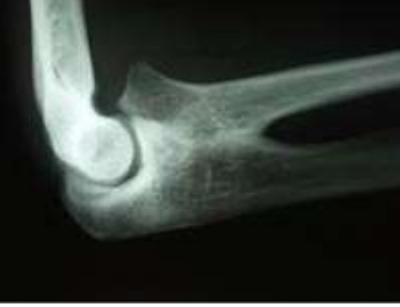

Sinostosi radio-ulnare prossimale congenita

E’ una sinostosi radio-ulnare prossimale congenita (FIG. A) con deficit di supinazione (Fig. B) che da qualche mese presentava una instabilità anteriore del gomito oltre i 90° di flessione con tre episodi di lussazione che hanno richiesto riduzione in narcosi.Intervento proposto : Accesso anteriore e previo isolamento e neurolisi ampia del nervo radiale, resezione generosa del capitello radiale ed osteotomia derotativa del radio sfruttando il predetto accesso e dell’ulna nel tentativo di portare il polso ad un atteggiamento funzionale più favorevole risolvendo nel contempo il problema di instabilità del gomito. Il pz. non ha ancora deciso di accettare l’intervento.